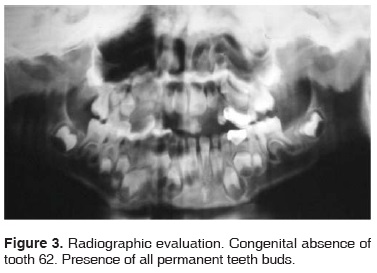

Radiographically, the following could be observed: congenital absence of tooth number 62, presence of all permanent tooth buds; 11,12, 13, 14, 15, 16, 17, 21, 22, 23, 24, 25, 26, 27, 31, 32, 33, 34, 35, 36, 37, 41, 42, 43, 44, 45, 46 and 47 (Figure 3).